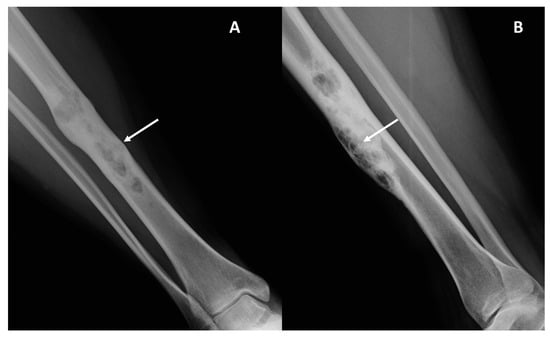

- Periosteal reaction (present/absent, aggressive or non-aggressive, and type); please see specific references for extensive explanations [11].

| Radiological Pattern: Lytic (0), Mixed (1), Sclerotic (2) | Mixed (9), lytic (6), sclerotic (1) | Mixed (3), lytic (3) | 0.69 |

| Periosteal reaction: absent (0), non-aggressive (1), aggressive (2) | Absent (13), Non-aggressive (2), aggressive (1) | Absent (2), Non-aggressive (2), aggressive (2) | 0.24 |

| Lodwick type (I, II, IIIA, IIIB) * | II (1), III A (11), III B (4) | III A (5), III B (1) | >0.99 |